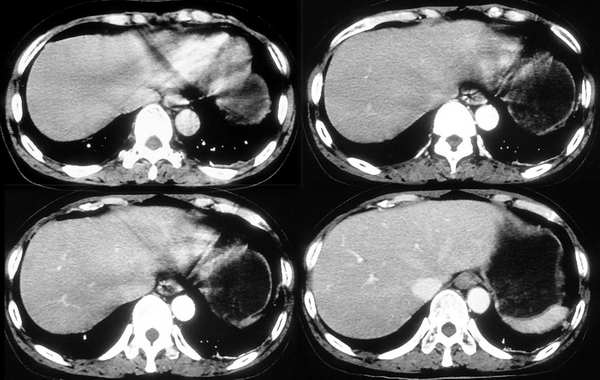

[br]请问战友,肝左叶低密度影和增强后杂乱无章的血管是什么?这是正常的吗?

以下是引用向医生在2005-11-3 21:54:00的发言:[br][br] 我觉得这例除了胆囊结石可以肯定外,肝左叶低密度区考虑为病灶尚不可靠。[br] 在b超下,早期肝脓肿者肝内见较强回声,界限欠清、模糊、形态不规则,如果有坏死液化才会出现低回声,而本例超声下已见低回声,如果真是这种情况的话就是说明病灶内已有坏死液化,这些液化区在ct增强下应该表现为低密度影,本例增强并无这样改变,所以b超的结果可不可靠值得怀疑。[br] 胆囊结石合并胆囊炎也可出现畏寒、发热及白细胞增高等,抗炎治疗后也可症状缓解,不一定非要用肝脓疡来解释。